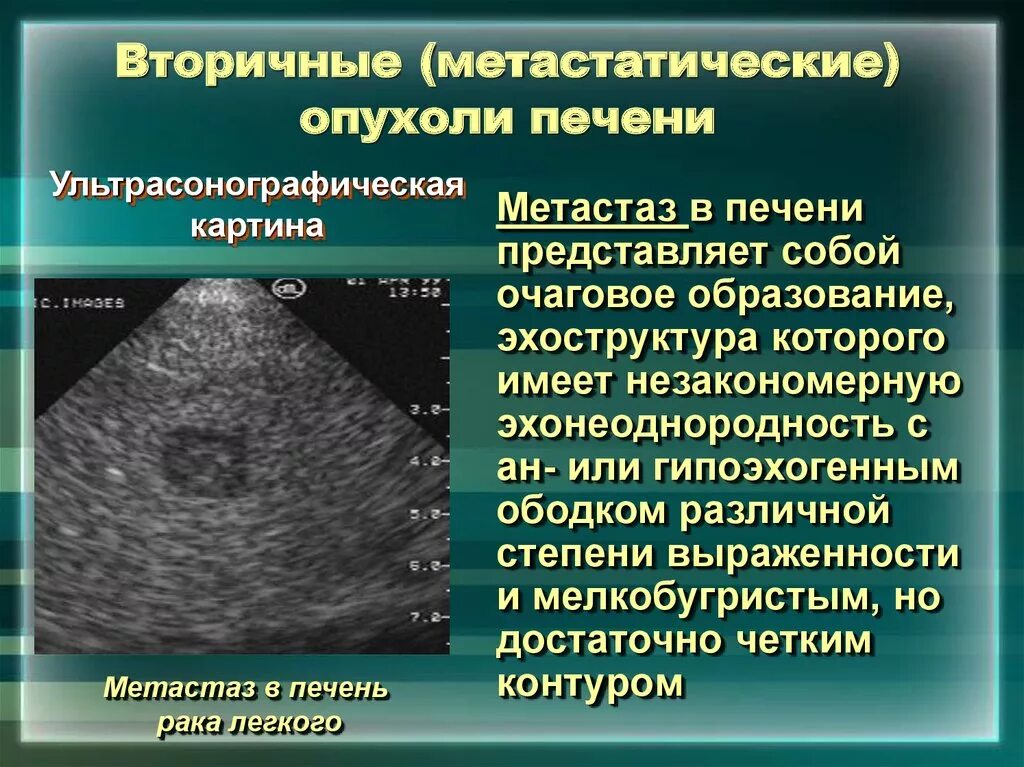

Доброкачественная опухоль. Доброкачественныеопкхоли. Клетки, образующие доброкачественную опухоль:. Строение доброкачественной опухоли. Гиповаскулярные метастазы печени кт. Опухоль желудка метастазирование.

Гиповаскулярные метастазы печени кт. Опухоль желудка метастазирование. План обследования ободочной кишки. Диагноз опухоли ободочной кишки. Диагностические методы исследования ободочной кишки. Алгоритмы диагностики заболеваний толстой кишки.

ПЭТ кт томограмма. Кт, ПЭТ И ПЭТ/кт. ПЭТ кт с контрастом. Скопление контраста ПЭТ кт. Метастатическое поражение печени. Метастатические опухоли печени. Злокачественные образования печени.

Метастатическое поражение печени. Метастатические опухоли печени. Злокачественные образования печени. Молочная железа маммография. Мастопатия на маммографии. Опухоль молочной железы маммограмма. Рик молочной железы маммографич.